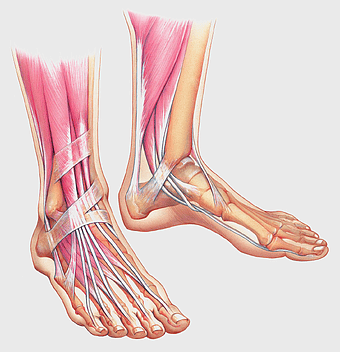

1434x1484px

human leg muscle illustration, foot anatomy muscle ankle bone, arches of the foot, tendon, foot skeletal structure, lower limb anatomy, calf muscle diagram -